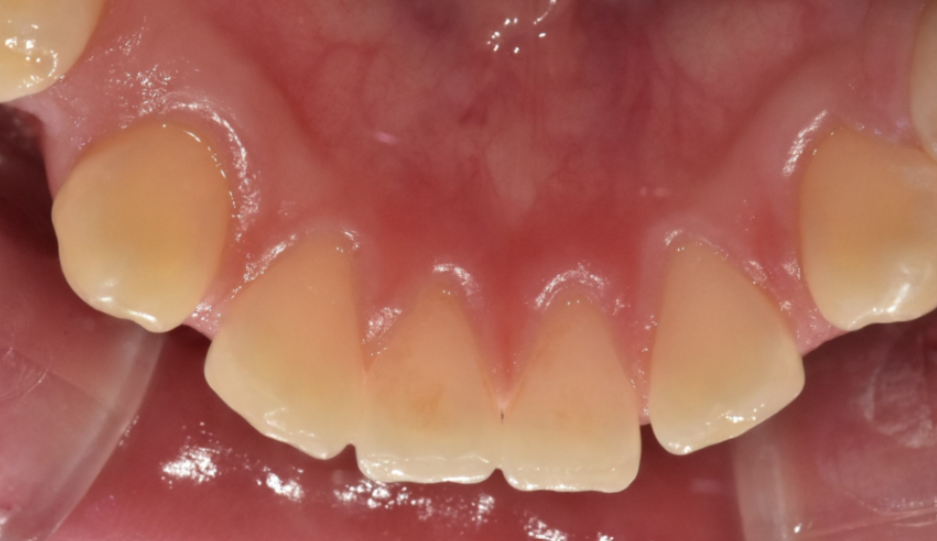

앞니가 몇개만 살짝 벌어졌다거나

어금니 교합에 문제가 없는 경우는 부분 교정으로 가능합니다.

이 경우 교정 기간도 짧아요.

단, 몇개 치아만 움직이는 것이다 보니

혀 습관이 개선된다거나

교합 문제는 해결되지 않습니다.